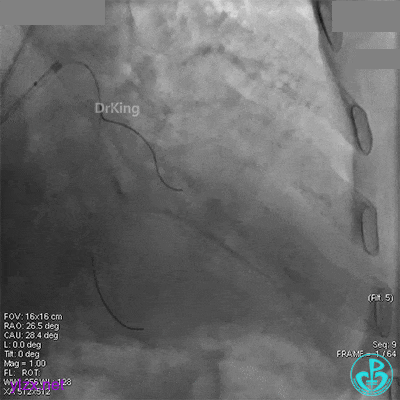

XB 3.0指引导管到位,导丝通过闭塞段至回旋支远段。

另一导丝保护分支,1.5×15mm球囊扩张闭塞处后造影,前向血流缓慢,远端分支血管没有充分显影。

1.5×15mm球囊扩张后前向血流缓慢的原因要高度怀疑慢血流。